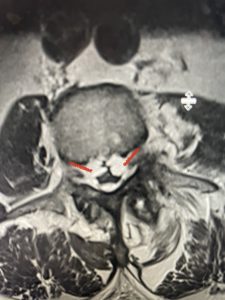

The next patient is a 71 year-old male with a two-year history of low back pain and lower extremity pain, numbness and weakness. His left leg was worse than the right. He had had five epidurals with no improvement. He also had tried physical therapy and medicines but nothing helped. He also felt that over the last three weeks he had gotten worse. He also had recently had some decreased sensation of bladder fullness and difficulty with bowel movements. MRI revealed a very tight L2-5 stenosis with an extruded L3-4 disc fragment (Fig 3).

(Figs 3a) Sagittal (a) and Axial (b) T2-weighted lumbar MRI demonstrating severe spinal stenosis L2-5 (arrow)and extruded disc at L3-4 on axial image (arrow)

(Fig 3b)

He had concentric severe stenosis with severe compression of the lateral recess and foramen at L3-4 secondary to the superimposed disc herniation. The fact that he had gotten worse with subtle cauda equina features with an extremely tight canal, he underwent a decompressive laminectomy. We also augmented his laminectomy with an in situ fusion from L3-5 as he was relatively young, with more time to reform arthritis, and had been unstable enough to extrude a disc fragment. By placing “bone dust” or bone material along the sides of the spine, specifically laying it across the transverse processes after they have been drilled to bleeding bone, you provide an environment where bone formation is induced to connect the segments, stabilize them, and thereby reduce the signal to make more arthritis as that signal is still present despite the laminectomy. What was interesting was that we encountered a large extruded disk fragment that was significantly contributing to his compression which is often not found in patients in this age bracket. Post operatively he had much improvement of leg pain.